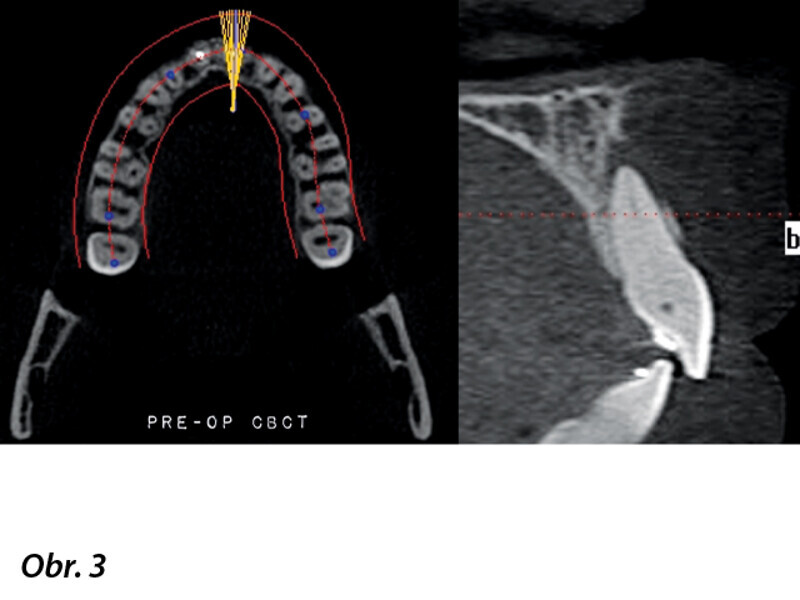

Navigovaný endodontický přístup u kalcifikovaných frontálních zubů: Kazuistika